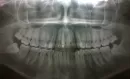

Извините за плохое качество фото. Снимки: после установки постоянной пломбы, затем в январе 2016 года и панорамный снимок 28 апреля 2016 года.

По этому снимку однозначно говорить невозможно. Апекс немного изменён и имеет воспаление. Но я Вам рекомендую сделать К/Т для полной ясности картины.